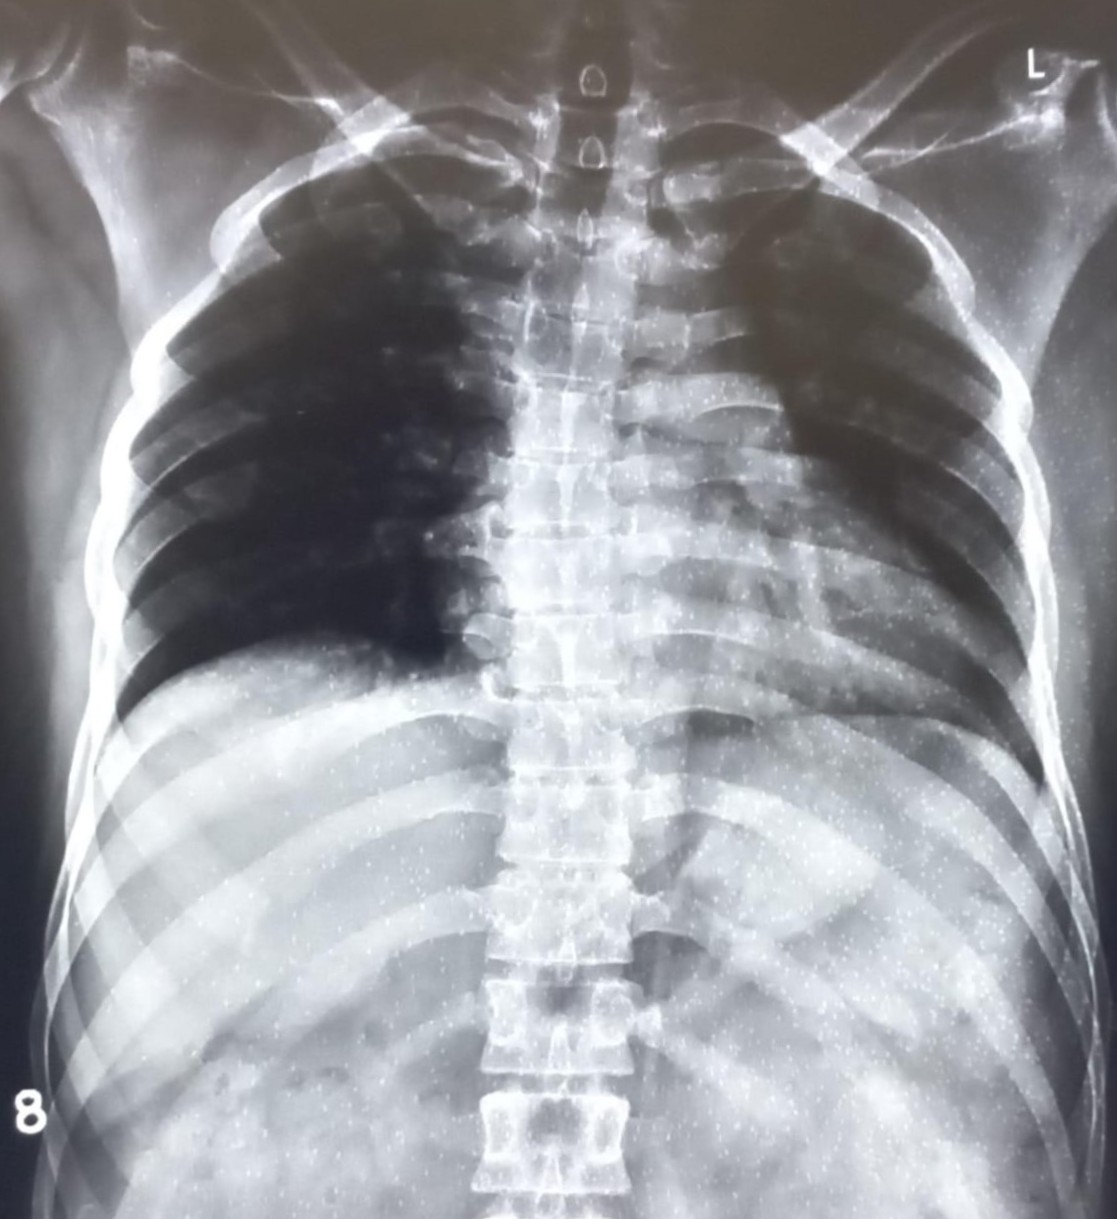

| 4437 | IGGMC, Nagpur, Nagpur | P2 | 29-35 | narendra parate | Consent taken on Paper | 25 Yrs. |

Provisional Diag : Cronic Cough

Final Diag : pleural effusion |

TB Case (Confirmed) | right CP angle blunted, suggestive of right sided pleural effusion | Abnormality visible on x-ray |